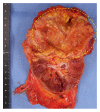

Case presentation: A 76-year-old woman was referred to our department to undergo further examination for a left renal tumor that was detected by ultrasonography. Dynamic contrast computed tomography (CT) revealed an enhanced tumor in the upper renal parenchyma. Laparoscopic radical nephrectomy was performed based on a preoperative diagnosis of renal cell carcinoma. Histological sections showed the aggregation of foam cells; thus, XGP was diagnosed.

Conclusion: We herein report a rare case of XGP in the upper pole of the kidney, which might have been associated with an incomplete double ureter.